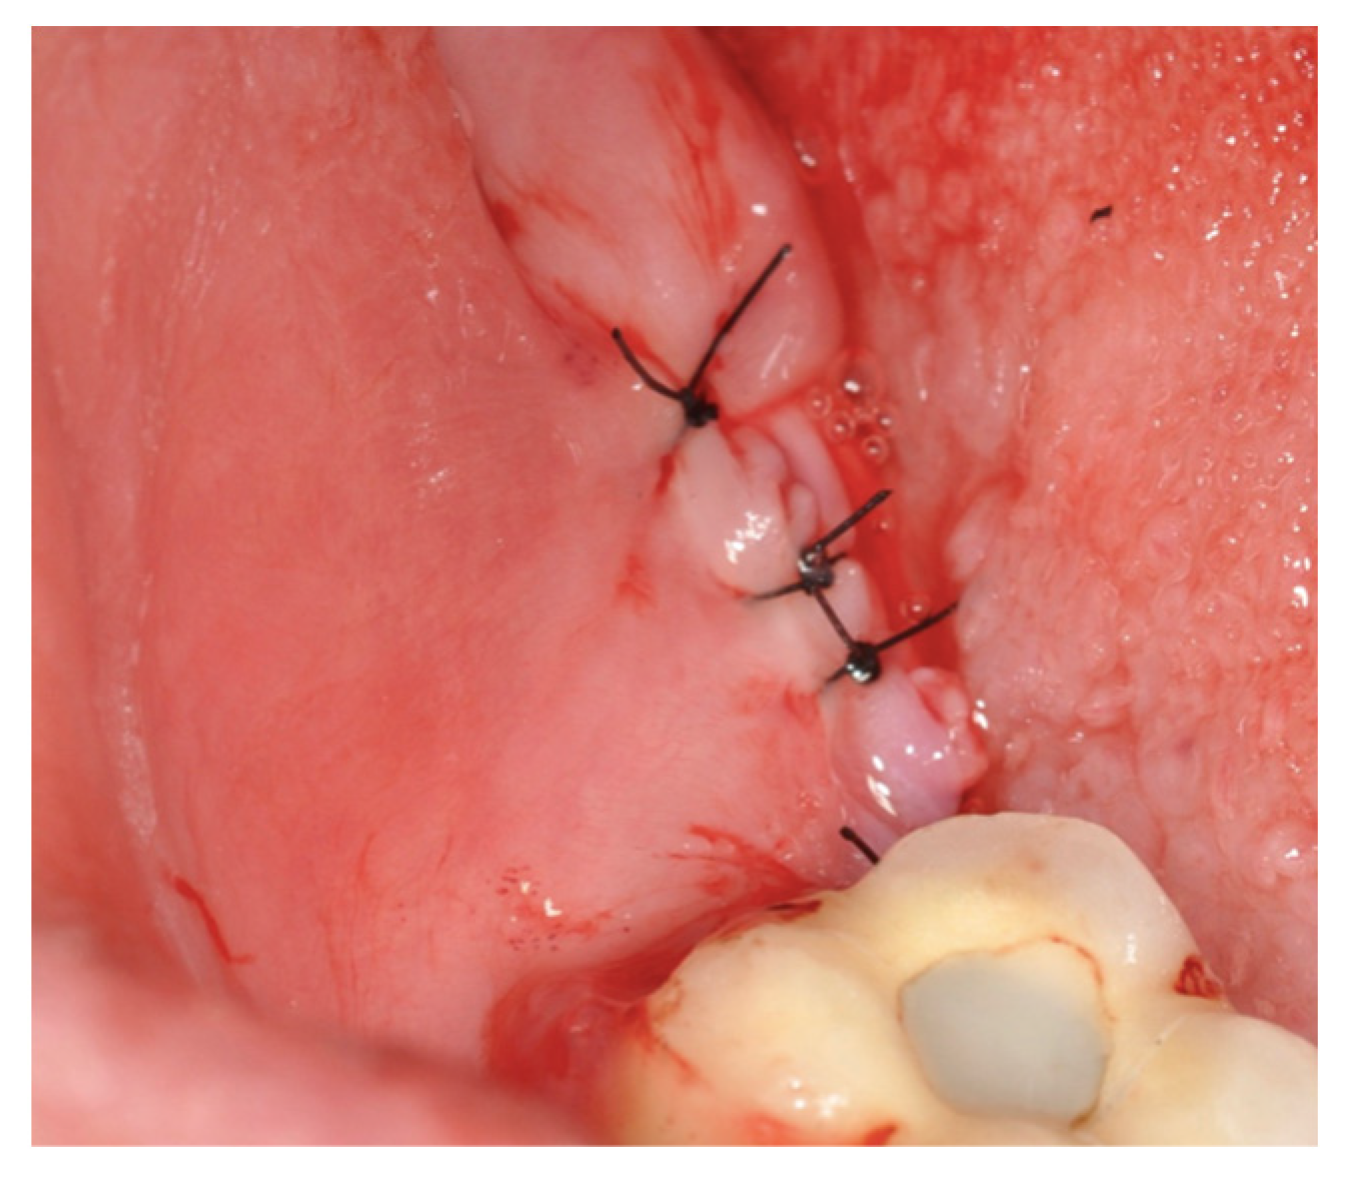

2.2. Surgical Technique